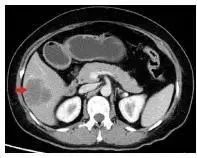

腹部增强CT检查显示肝VI段见边界清、低密度肿块影、环形强化(图 2),再行PET-CT检查显示肝Ⅵ段类圆形、低密度肿块影、糖代谢不高、延迟代谢略有减低。排除后,行经腹腔镜右肝肿瘤根治术,术中见肿物位于肝Ⅵ段,直径约6 cm,距肿瘤1 cm,完整切除。

图 2 CT检查肝VI段占位